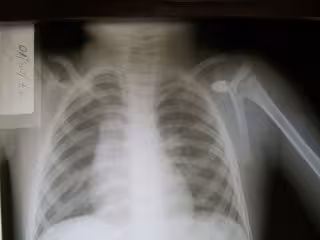

Mañana se celebra la primera edición del 'Día Europeo de la Radiología'

Radiografía, rayos X, radiología, técnicas de imagen

Con el propósito de divulgar la Radiología al público en general y de concienciar sobre la importancia que la Imagen Médica tiene en sus vidas, la Sociedad Europea de Radiología celebra mañana la primera edición del 'Día Europeo de la Radiología', coincidiendo con el aniversario de la muerte de Wilhem Conrad Roentgen, que es considerado el padre de la disciplina por descubrir los rayos X en 1895.

La elección del día 10 de febrero como fecha de celebración se ha elegido para establecer un lazo entre los comienzos de la radiología y el estado actual en que se encuentra porque, como recuerdan los radiólogos, la Imagen es una herramienta "indispensable" en la medicina moderna, aunque "muy pocos" pacientes conocen todavía su verdadera importancia.

La mayoría de la gente conoce los rayos X, lo tradicional en radiología, lo que "no es tan conocido es que los continuos avances y desarrollos tecnológicos en la Imagen Médica han convertido a la Radiología en una especialidad que no sólo detecta los problemas del paciente, sino que contribuye significativamente al tratamiento y posterior recuperación", recuerdan desde la Sociedad Española de Radiología Médica (SERAM).